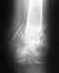

3 года назад попал в ДТП, в результате чего получил фрагментарные оскольчатые переломы обеих костей голени со смещением. Был произведен остеосинтез большеберцовой кости, но пластина через 3 месяца сломалась, затем поставили аппарат Иллизарова, через 8 месяцев образовался "ложный сустав", опять поставили пластину, через год сняли и опять перелом на том же месте, сейчас опять с пластиной. Почему плохо срастается кость? Сейчас малоберцовая сломана, но остеосинтеза не проводили на малоберцовую, я чувствую при ходьбе боль, нужно ли поставить пластину на малоберцовую, или всю жизнь ходить со сломанной костью и ощущать боль?

Кость срастается плохо потому, что в реззльтате травм и открытых операций нарушено кровоснабжение концов отломков, повреждена скелетогенная ткань. Несращение малоберцовой кости на результат не влияет. Чтобы не было рецидивов, лучше фиксирвовать не пластиной. а внутрикостным стержнем с блокированием винтами.